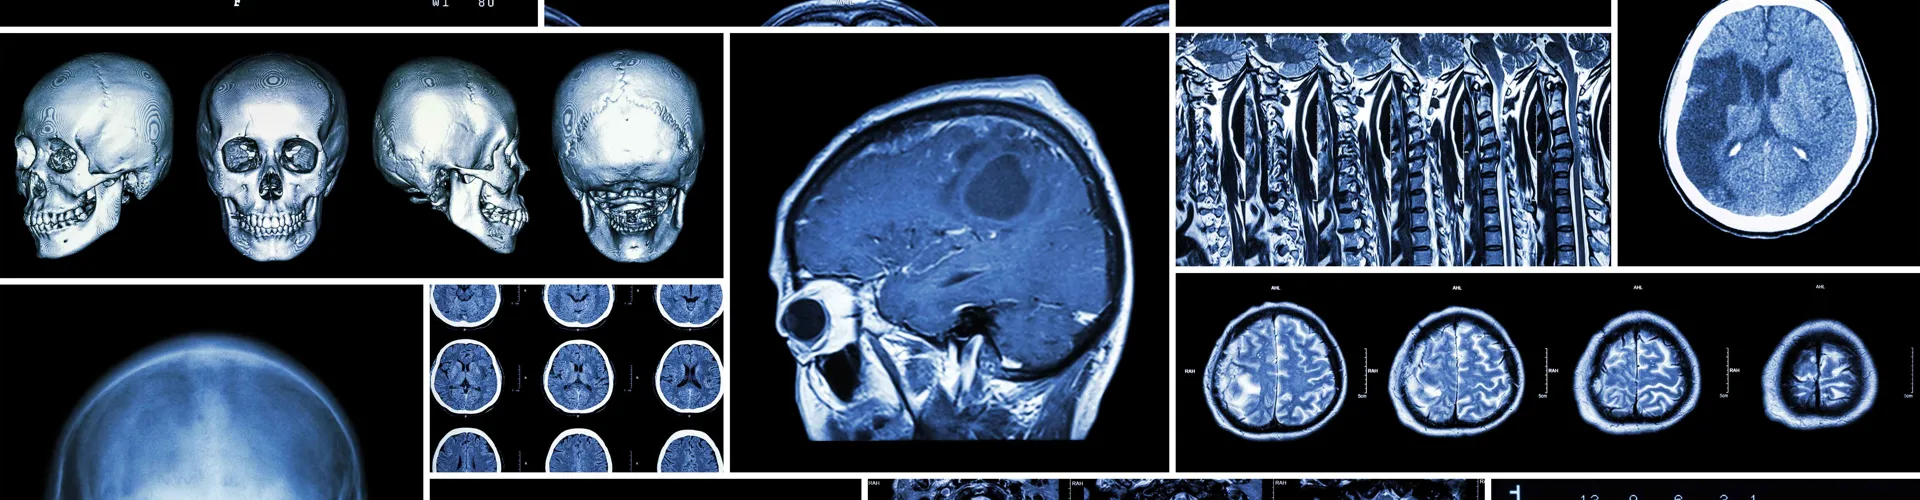

The lesson begins with students being provided with the medical records of eight patients. They will also review several different imaging techniques including: CAT, Gamma cameras, MRI, PET, Thermology, Ultrasound and X-rays.